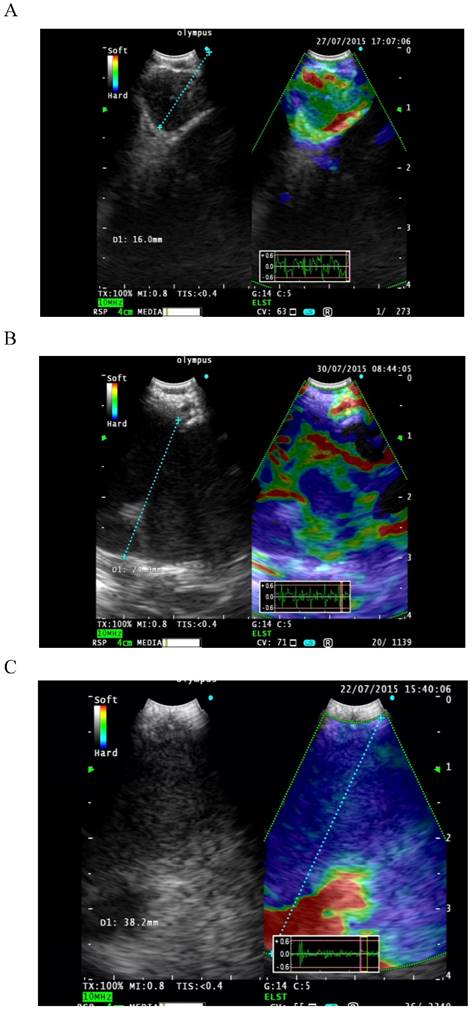

Classification of LNs was performed. Elastographic patterns were described according to the dominant colors and their distribution within the target LN. This description formed the basis for the following classification of elastographic types: Type 1 [Figure 1A]: predominantly non-blue (green, yellow and red). Type 2 [Figure 1B]: part blue, part non-blue (green, yellow and red). Type 3 [Figure 1C]: predominantly blue. Only LNs with adequate lymphocytes or those with a definitive diagnosis were included for data analysis.

Figure 1

A: Type 1 predominantly non-blue (green, yellow and red). B: Type 2 part blue, part non-blue (green, yellow and red). C: Type 3 predominantly blue.